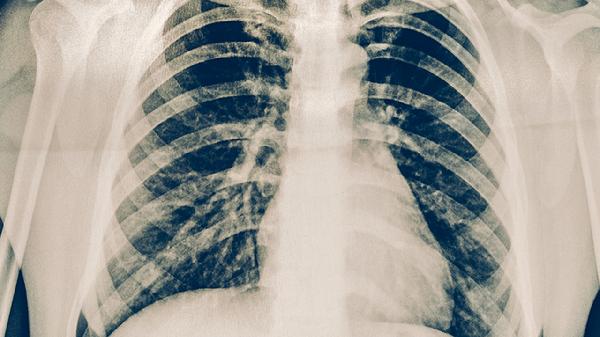

肺結(jié)核與肺癌并存時(shí)需根據(jù)病情采取抗結(jié)核治療聯(lián)合肺癌綜合治療。主要干預(yù)方式包括抗結(jié)核藥物治療、肺癌手術(shù)切除、放射治療、化學(xué)治療及靶向治療。兩種疾病并存可能加重肺部損傷,需由呼吸科與腫瘤科聯(lián)合制定個(gè)體化方案。

確診活動(dòng)性肺結(jié)核后需立即啟動(dòng)規(guī)范抗結(jié)核治療,常用藥物包括異煙肼片、利福平膠囊、吡嗪酰胺片等聯(lián)合用藥方案。治療期間需定期監(jiān)測(cè)肝功能,避免藥物性肝損傷。若肺結(jié)核處于穩(wěn)定期且肺癌需優(yōu)先處理時(shí),可暫緩抗結(jié)核治療,但需密切觀察結(jié)核活動(dòng)跡象。

對(duì)于早期非小細(xì)胞肺癌且肺功能允許者,手術(shù)切除是首選治療方式。肺葉切除術(shù)或楔形切除術(shù)可在清除癌灶同時(shí)切除合并結(jié)核的肺組織。術(shù)前需評(píng)估結(jié)核病灶是否處于活動(dòng)期,活動(dòng)性結(jié)核可能增加術(shù)后支氣管胸膜瘺風(fēng)險(xiǎn)。術(shù)后仍需完成抗結(jié)核全程治療。